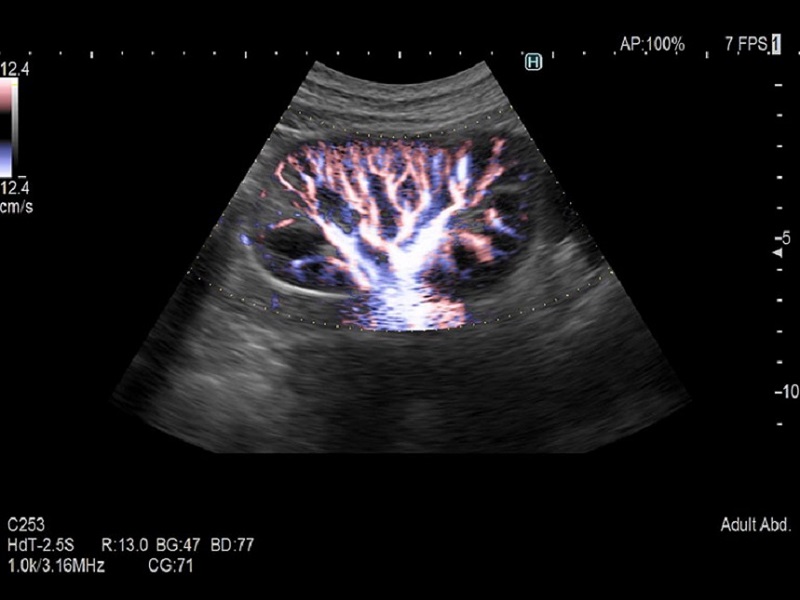

Dormed Hellas AR65 – OB 4D Dormed Hellas AR65 – Kidney

Dormed Hellas AR65 – Cardio CF Dormed Hellas AR65 – Cardio M-mode